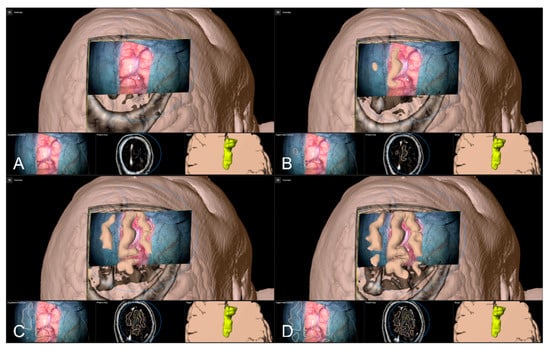

After calibration of the surgical microscope, AR-support including all pre-segmented objects is available. Outlined objects, such as the tumor or vascular or functional risk structures, can then be visualized using the AR display by superimposing the 3D objects in the operating microscope by the integrated HUDs. In parallel, multimodal fused image sets are visualized in the Cranial Navigation Element (Brainlab, Munich, Germany) on a monitor close to the surgical field. In addition, within the Microscope Navigation Element (Brainlab, Munich, Germany) objects can be displayed, e.g., superimposed on the microscope video or within a probe’s eye view of the registered image data. Alternatively, the microscope video can be superimposed on a 3D visualization of the patient data including all objects and relevant pre-segmented structures intuitively relating the microscope video frame and 3D anatomy (see Figure 3).

Figure 3.

After calibration of the microscope, besides HUD-based visualization within the microscope, the Microscope Navigation Element (A) and Cranial Navigation element (B) are displayed on monitors close to the surgical field. The microscope application allows for a visualization of outlined objects (yellow: tumor, blue: precentral gyrus, corticospinal tract) superimposed on the microscope video (A, top), or probe’s eye view, target view or outlined 3D anatomy in relation to the microscope video frame (A, bottom, left to right). In parallel, in the navigation application multimodal fused image sets with outlined structures are visualized in, e.g., axial, coronal, and sagittal view (B).